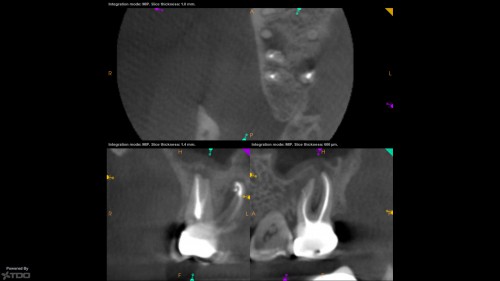

73yof in today for obvious reasons. I just can't figure this out…let alone why anyone […]